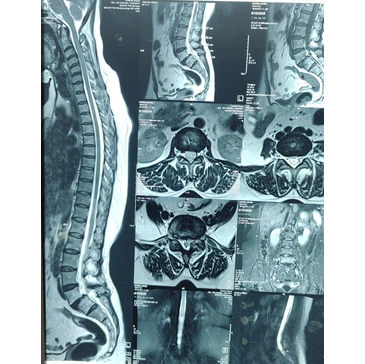

• Imaging tests to identify affected spinal area

• Diagnostic imaging to evaluate spine condition

Diagnosis typically includes clinical examination and imaging such as X-ray, MRI, or CT scan.